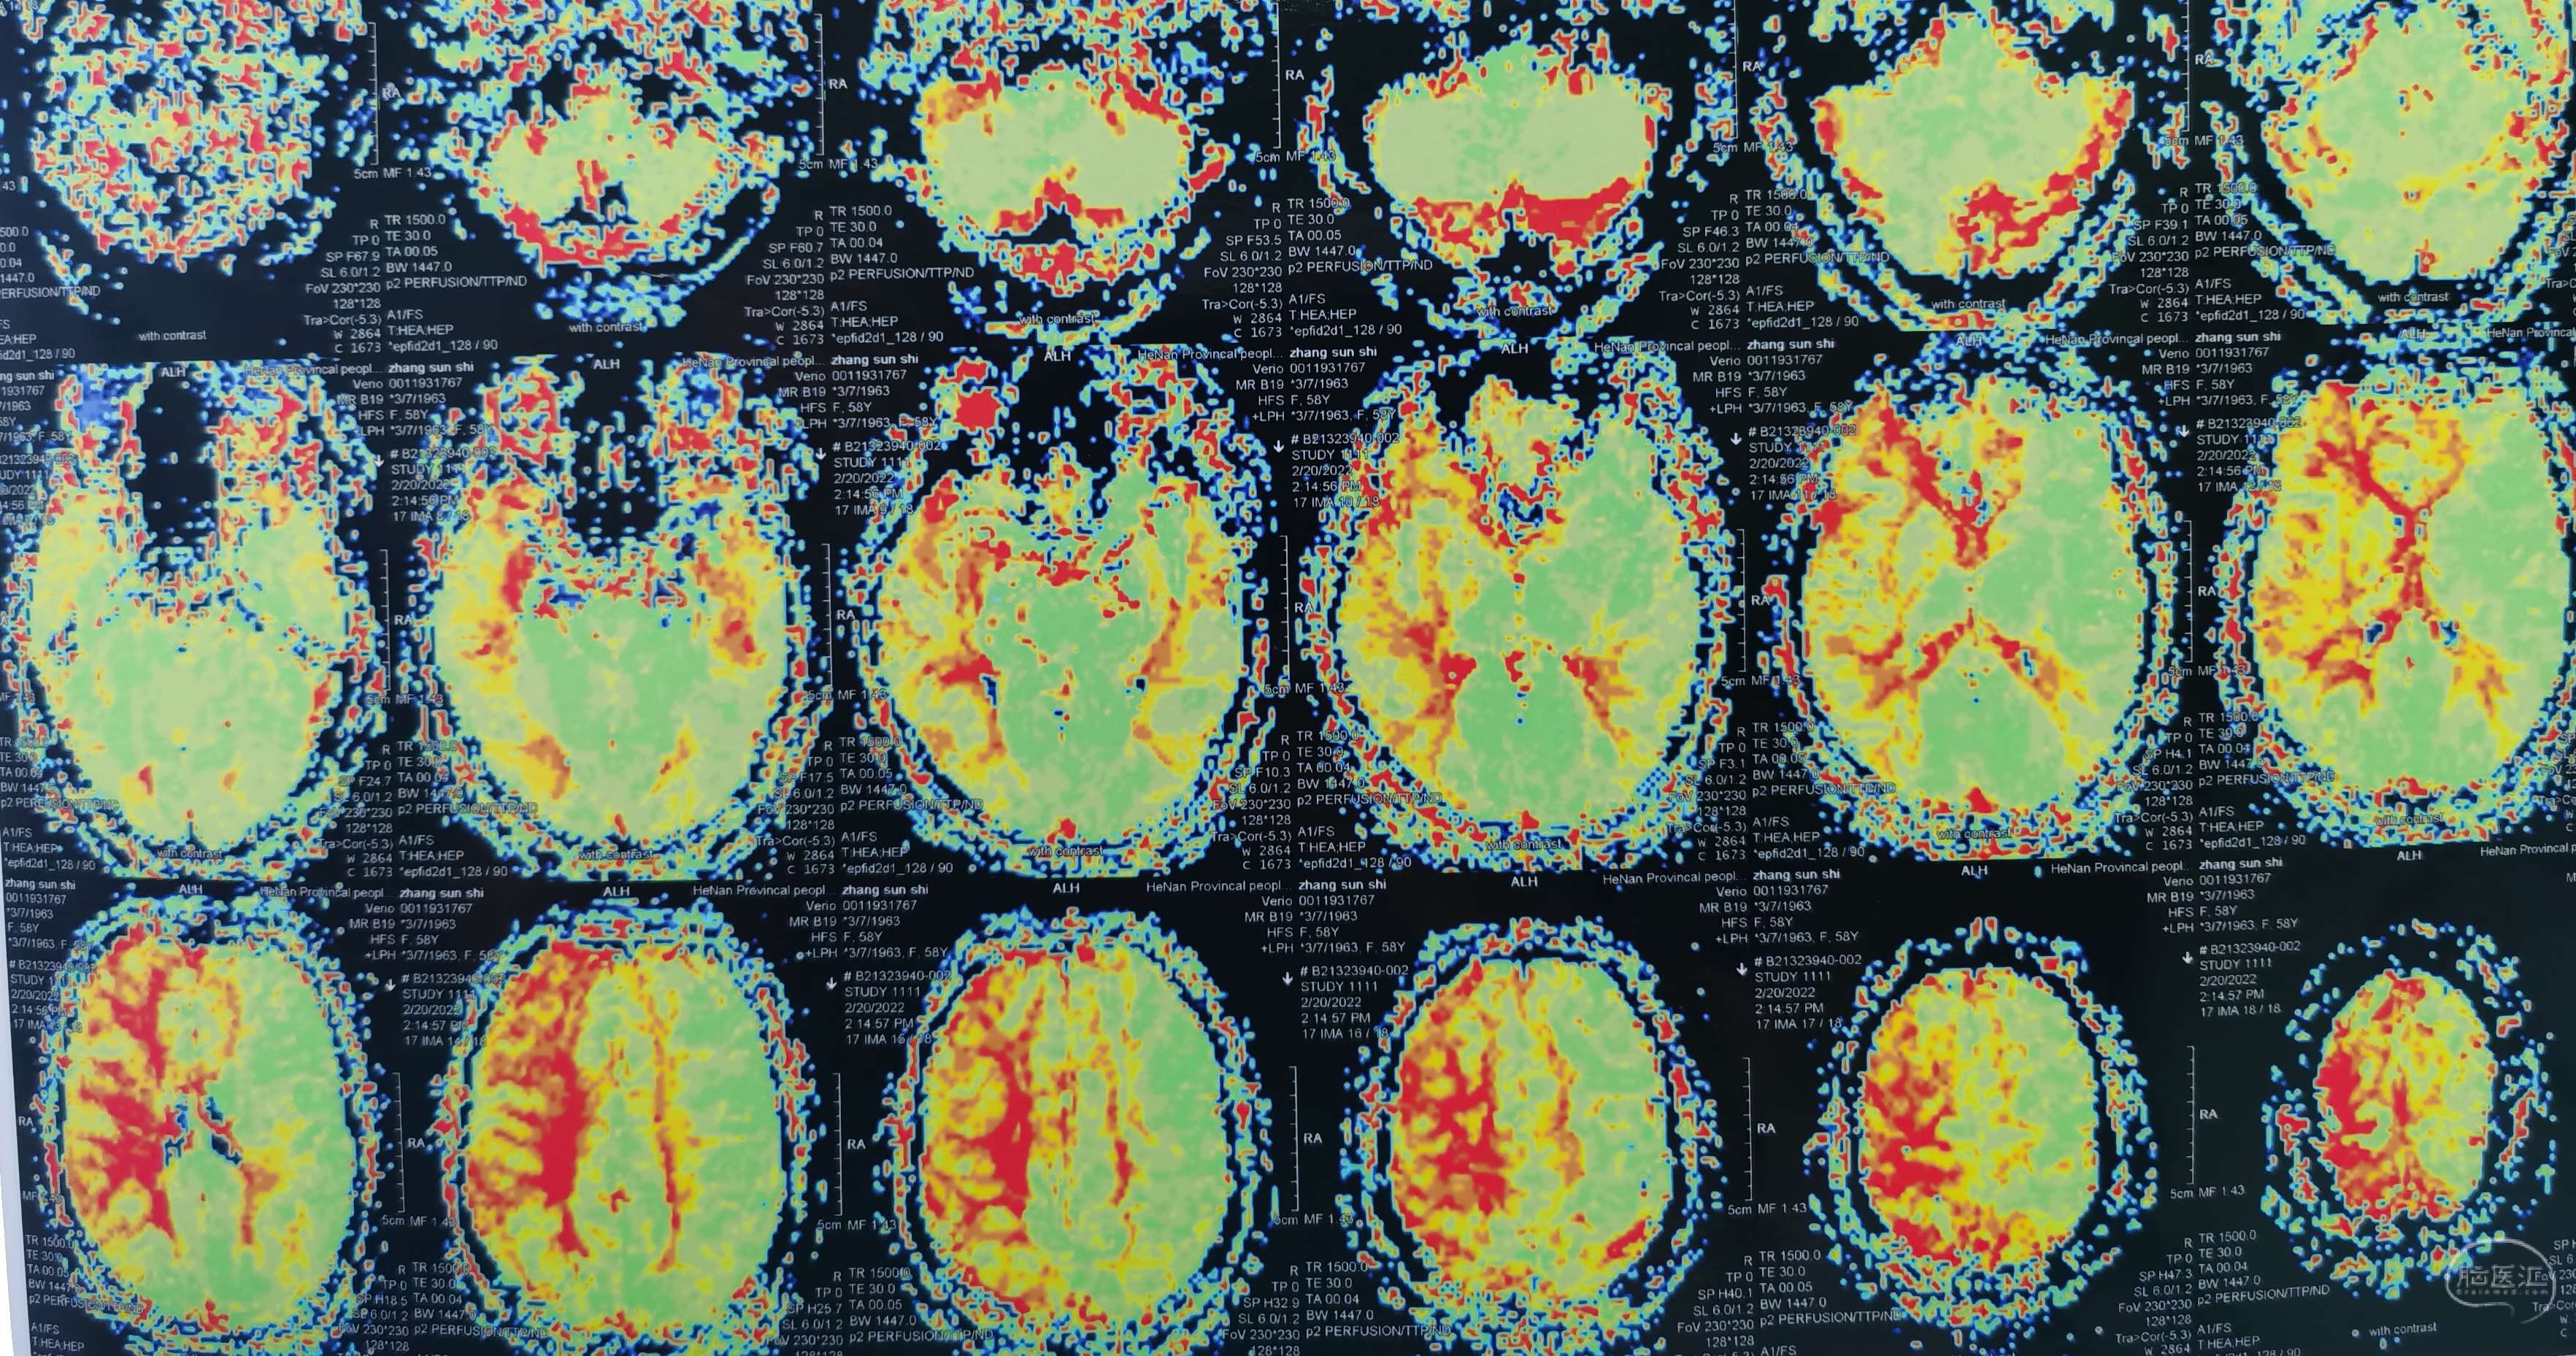

脑灌注提示:左侧大脑半球低灌注缺血。

脑灌注提示:右侧大脑半球低灌注缺血。

脑灌注提示:双侧大脑半球低灌注缺血。

脑灌注提示:双侧大脑半球低灌注缺血。

脑灌注提示:双侧大脑半球低灌注缺血。